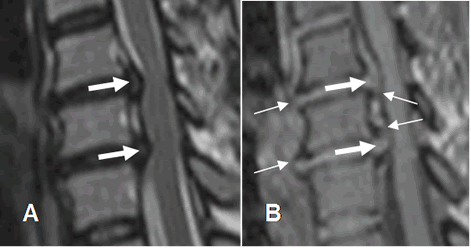

La degeneración del disco según el método de Pfirrmann, se gradúa en T2 así: (26). (Fig 113).

Los discos con una altura normal previa a la cirugía (Grados I a III) tienen mayor riesgo de recurrencia de hernia, que los que tienen cambios degenerativos severos. (Grados IV y V). (26).

Fig 113. Tipos de degeneración del disco.

A: RM axial en T2. Disco con diferenciación entre el núcleo pulposo y el anillo fibroso.

B: RM axial en T2. Disminución en la señal del núcleo pulposo, persistiendo banda hipointensa central.

C: RM axial en T2. Zona central del disco con señal intermedia.

D: RM axial en T2. Disco hipointenso, sin poder diferenciar el núcleo pulposo del anillo fibroso.

E: RM axial en T2. Disco hipointenso, con pérdida del espacio.

En B existe una hernia extruida y en C y D, una hernia central.